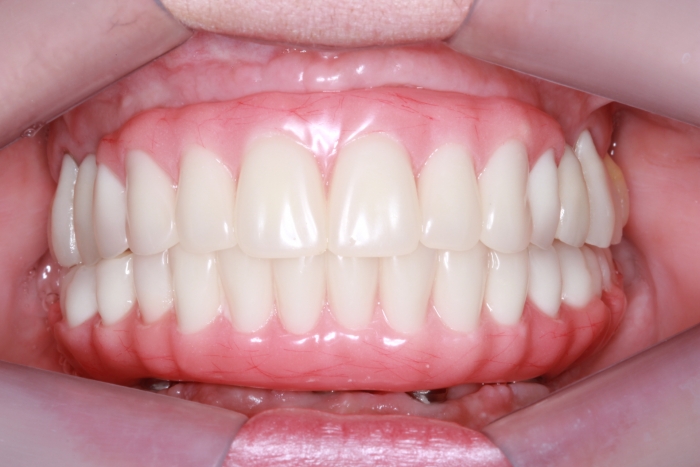

Próteses fixas definitivas em resina em Outubro de 2016 - Clínica Cliniface

Próteses fixas definitivas em resina em Outubro de 2016